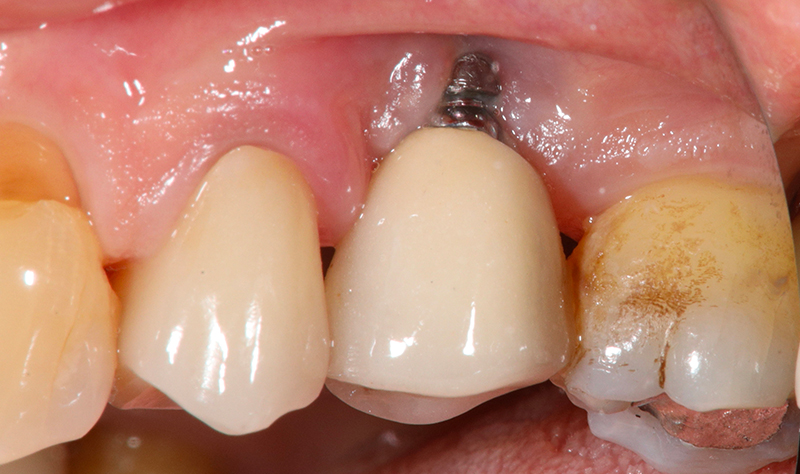

Nell'ultimo anno le è stata riscontrata complicanza a carico dei tessuti peri-implantari di elemento zona 25. L'esame visivo e lo status fotografico (Figs. 1-2) evidenziano un’alterazione dello stato dei tessuti molli peri-implantari, che guida il clinico verso un’indagine più approfondita tramite acquisizione RX. Si esegue perciò esame radiografico del sito coinvolto (Fig. 3), da cui risulta un’importante riassorbimento osseo a carico dell’impianto. Si procede con sondaggio peri-implantare profondo, con la finalità di definire estensione e forma del difetto (Fig. 4) e, associandolo all’esame radiografico, di eseguire la conta delle spire implantari esposte. Tale manovra verrà effettuata con l’impiego di anestetico da irrigazione, data la nota dolorolabilità in peri-implantite, in quanto tale patologia determina la perdita di barriere connettivali e pertanto la penetrazione in osso durante il sondaggio.

Dettaglio dell'elemento interessato da perimplantite

Fig. 2 - Dettaglio dell'elemento interessato da peri-implantite con evidente situazione clinica patologica.